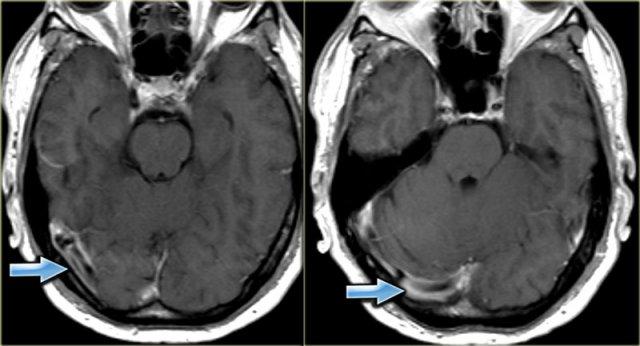

Dấu hiệu cục máu đông tăng tỷ trọng (2)

Hình ảnh tĩnh mạch vỏ não bị huyết khối biểu hiện dưới dạng một dải hoặc đường tăng tỷ trọng hình dây thừng còn được gọi là dấu hiệu dây thừng (cord sign).

Một thuật ngữ khác thường được sử dụng là dấu hiệu mạch máu tăng tỷ trọng (dense vessel sign).

Dấu hiệu cục máu đông tăng tỷ trọng (3)

Hình ảnh bên trái là của một bệnh nhân có nhồi máu xuất huyết ở thùy thái dương (mũi tên đỏ).

Lưu ý xoang ngang tăng tỷ trọng do huyết khối (mũi tên xanh dương).